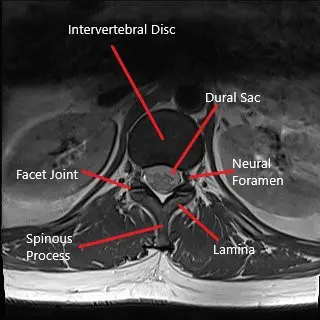

Axial section of lumbar spine MRI.

The diagnosis of sciatica in pregnancy is made clinically by the physician. Radiological studies such as x-ray are avoided in pregnancy. MRI is generally safe in pregnancy but is only done in case of worsening motor/sensory weakness and during planning of the surgery. X-ray may be done if the benefits outweigh the potential risks.